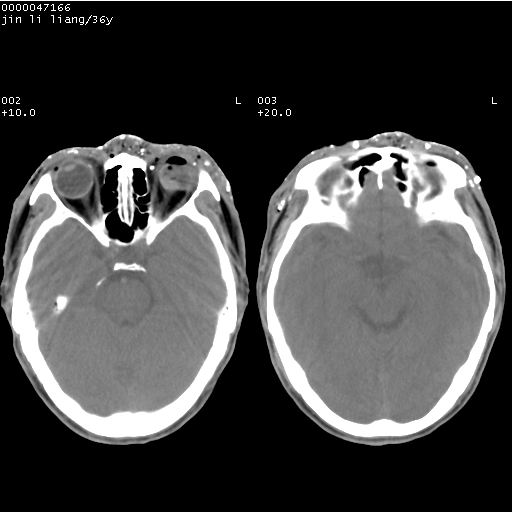

患者 男,36岁。头面部“土炮”炸伤。pe:面目全非,伤口流血不止。

临床诊断:头面部外伤。

颅脑ct轴位平扫(层厚、层距均为10mm),图像如下:

左眼球破裂,异物.

左眼球破裂,球内异物

左眼球内容物浑浊其内见气体影,头面部异物.

左眼球破裂并异物,眶周、额顶部头皮及软组织挫伤并异物

迎面一炮,满脸开曝。额顶部头皮及软组织挫伤并异物,左眼球破裂积气并异物,典型的面目全非,惨不忍睹。

左眼球破裂积气并异物,眶周、额顶部头皮及软组织挫伤并异物,右侧眼环前内分异物

1左侧眼球破裂并积气,球内、框内异物。

2额部顶部软组织伤。